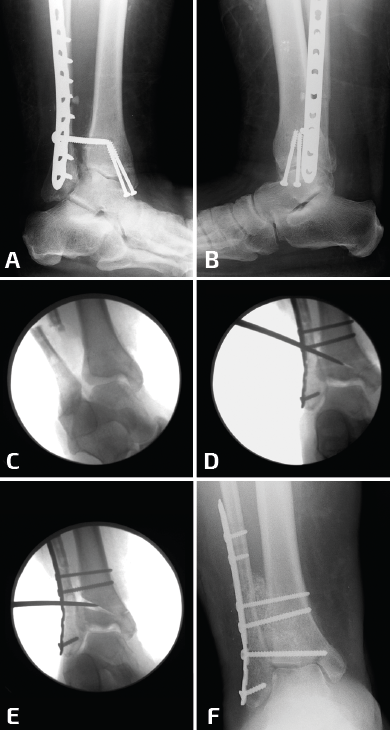

Durante la reconstrucción de la pseudoartrosis, es esencial realizar una artrotomía anterolateral para visualizar la reducción anatómica del peroné (Figura 1); sin embargo, el desbridamiento artroscópico de la articulación debe realizarse en forma simultánea no tanto para determinar el grado de artritis del tobillo, sino para tratar alguna lesión osteocondral no visible con la artrotomía anterolateral.

Figura 1. Cuando es necesaria una elongación significativa, se debe desbridar toda la sindesmosis anterior y dejar libre el peroné. Es indispensable para este paso un separador de láminas.

El tejido hipertrófico entre el maléolo interno y el astrágalo debe resecarse desde el receso interno para el correcto reposicionamiento del astrágalo. Esto se puede lograr por vía artroscópica o mediante una artrotomía anteromedial. Esto es importante tenerlo en cuenta, ya que una pequeña cantidad de tejido en la gotera interna puede bloquear el correcto desplazamiento medial del astrágalo dentro de la mortaja. La pseudoartrosis del peroné por lo general se asocia con un desplazamiento lateral del astrágalo, con un aumento del espacio claro medial, motivo por el cual se debe limpiar toda la gotera interna (Figura 2).

Figura 2. Aquí mostramos la técnica de elongación. Después del desbridamiento de la sindesmosis, se coloca la placa sobre el peroné y de colocan 2 o 3 tornillos distales (A, B). Se coloca un tornillo de 3,5 en el peroné proximal a la placa y el separador de láminas entre el tornillo y el borde proximal de la placa (C, D). En este caso, para corregir la consolidación viciosa del maléolo medial, se realizó una osteotomía (E) y el control de radioscopia intraoperatorio muestra una buena reducción de la sindesmosis (F).

La artrotomía interna se realiza mediante una incisión de 2 cm medial al tendón tibial anterior directamente sobre la gotera interna. La incisión se profundiza hasta llegar a la articulación, para luego resecarse el tejido sinovítico hipertrófico, la cápsula y el tejido fibrótico que se encuentra en la gotera interna.

Resulta de gran utilidad la utilización de una gubia, que se debe girar 180° para garantizar que el receso interno quede totalmente libre y que el astrágalo esté móvil. Posterior a esto, se intenta llevar el astrágalo a medial, para corroborar que la gotera se encuentre limpia por completo y poder trabajar posteriormente con tranquilidad en la corrección de la pseudoartrosis del peroné.